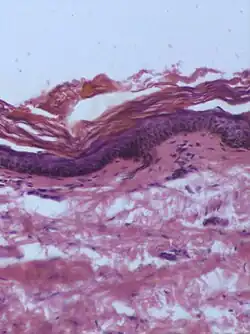

Specific dermatoscopic or histopathologic patterns

| Type | Characteristics | Photo- graphy |

Histo- pathology |

|---|---|---|---|

| Dysplastic nevus | Usually a compound nevus with cellular and architectural dysplasia. Like typical moles, dysplastic nevi can be flat or raised. While they vary in size, dysplastic nevi are typically larger than normal moles and tend to have irregular borders and irregular coloration. Hence, they resemble melanoma, appear worrisome, and are often removed to clarify the diagnosis. Dysplastic nevi are markers of risk when they are numerous, such as in people with dysplastic nevus syndrome. According to the National Institute of Health (NIH), doctors believe that, when part of a series or syndrome of multiple moles, dysplastic nevi are more likely than ordinary moles to develop into the most virulent type of skin cancer called melanoma.[19] | _-_crop.jpg) In this case, the central portion is a complex papule, and the periphery is macular, irregular, indistinct and slightly pink. |

Characteristic rete ridge bridging, shouldering, and lamellar fibrosis. H&E stain. Characteristic rete ridge bridging, shouldering, and lamellar fibrosis. H&E stain.

|